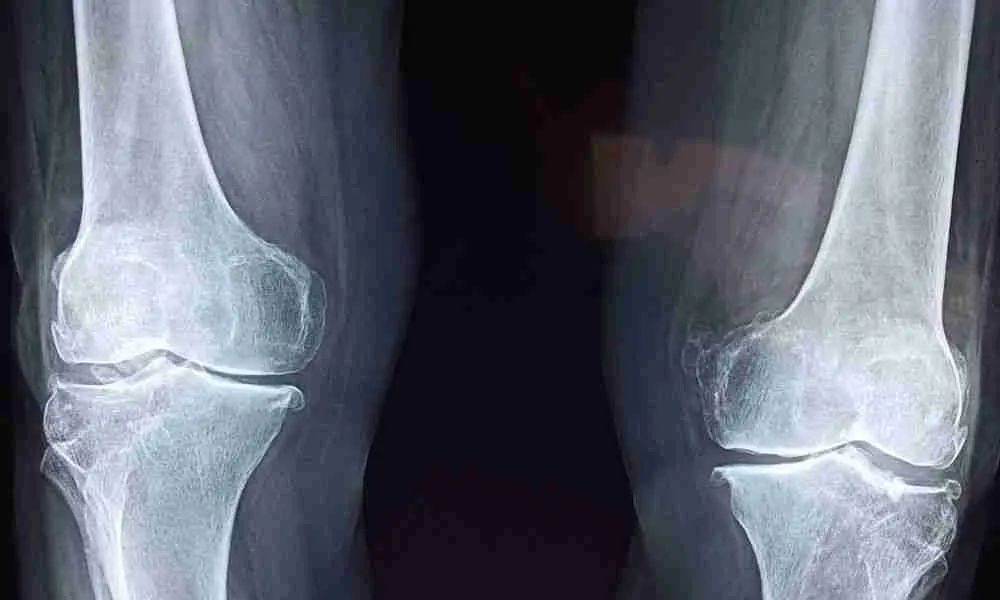

Knee arthritis, a degenerative joint condition, affects millions worldwide, reducing mobility and quality of life. As patients explore alternatives to traditional treatments, Platelet-Rich Plasma (PRP) therapy has gained traction as a promising intervention. This blog delves into the nuances of PRP for knee arthritis, including its success rates, what patients should know, and what they can expect from this innovative treatment.